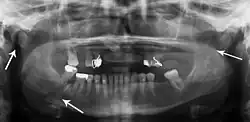

-

Towne's view of a bilateral condyle fracture. White arrow is a fracture on the neck of the condyle. Black arrow shows the condyle pulled to the medial. The same injury can be seen on the opposite side -